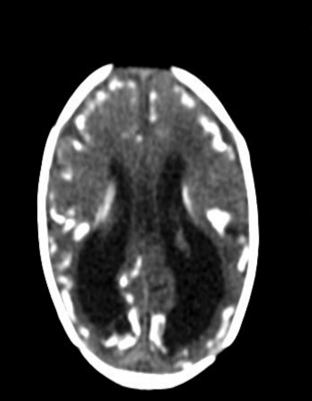

Encefalitis herpética en paciente con infección por SARS-CoV-2: Reporte de un caso

Monica Liseth Holguin Barrera, Lorena García Agudelo, Ledmar Jovanny Vargas Rodríguez, Natalia Fuentes Rodríguez

11-14